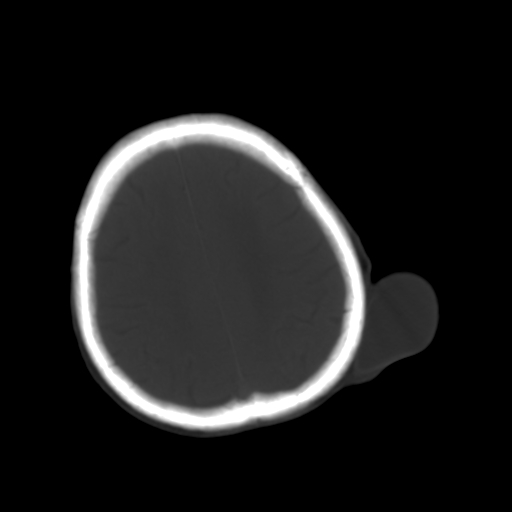

男,62岁,右侧肢体活动障碍不灵活三天,左侧头皮肿物十余年(ct值8hu)。

1)多发性腔隙性脑梗塞。2)脑白质病。3)脑萎缩。4)左侧枕顶部头皮下皮样囊肿,不排除脂肪瘤。